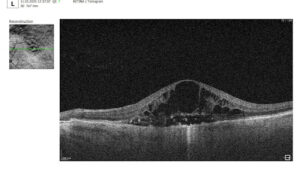

Figure 2. 6 mm OCT b-scan of the optic nerve head (ONH) region.

In contrast, macular OCT scans (Figure 3) focus on the central retina, providing detailed visualization of structures such as the foveal center, retinal layers, and macular biomarkers (such as drusen, hypertransmission, fluids etc). Since the macula is anatomically distinct from the optic nerve head, standard macular scans do not capture the ONH comprehensively.